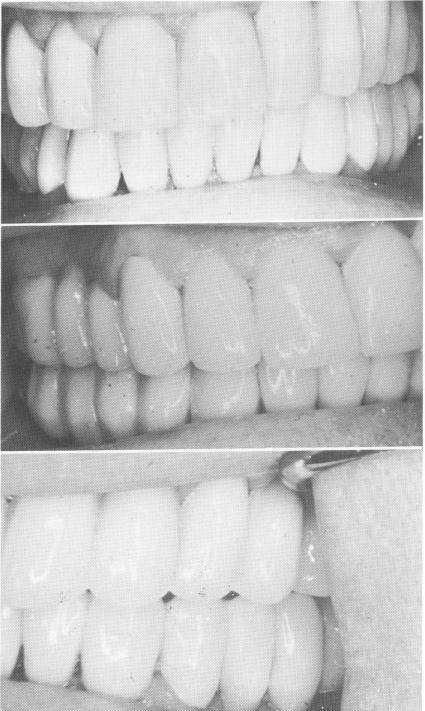

Fig. 11-57. The finished case carefully checked and balanced.

bone in the right posterior maxillary molar area (Fig. 11-55) . The natural teeth and implant abutments were then splinted (Fig. 11-56). The final prosthesis was seated with hard cement and the occlusion carefully checked and balanced (Fig. 11-57).